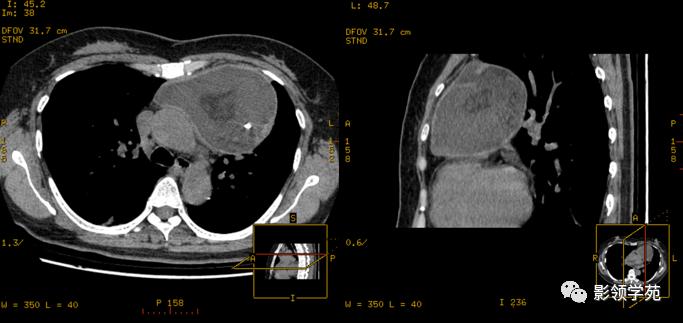

CT特征:

1、多数病灶与颈部甲状腺相延续,多位于气管前间隙,亦可伸入到气管及食道后方,冠状位及矢状位重建有利于显示连续关系。

2、肿块边缘较光滑,密度多不均匀,可见单发或多发低密度区,钙化较常见。

3、平扫CT值较高,增强后强化明显,且延迟较长时间。

4、多数病例纵隔内大血管及气管有推移表现。

矢状位重建显示更清晰